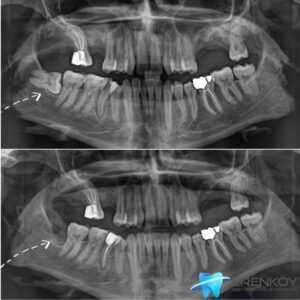

Diş implantı